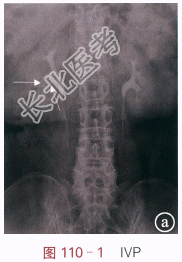

读片分析:图110-1IVP示右侧肾下盏及肾盂内有充盈缺损影,边缘欠规则;图110-2(动脉期)与图110-3(静脉期)示CT增强扫描后肾盂内病灶有强化,CT值分别约为91.3Hu和102.1Hu,平扫时(未提供)病灶CT约为30.6Hu;图110-4CTU示肾盂内充盈缺损。结合病史,可知患者为肾盂癌。